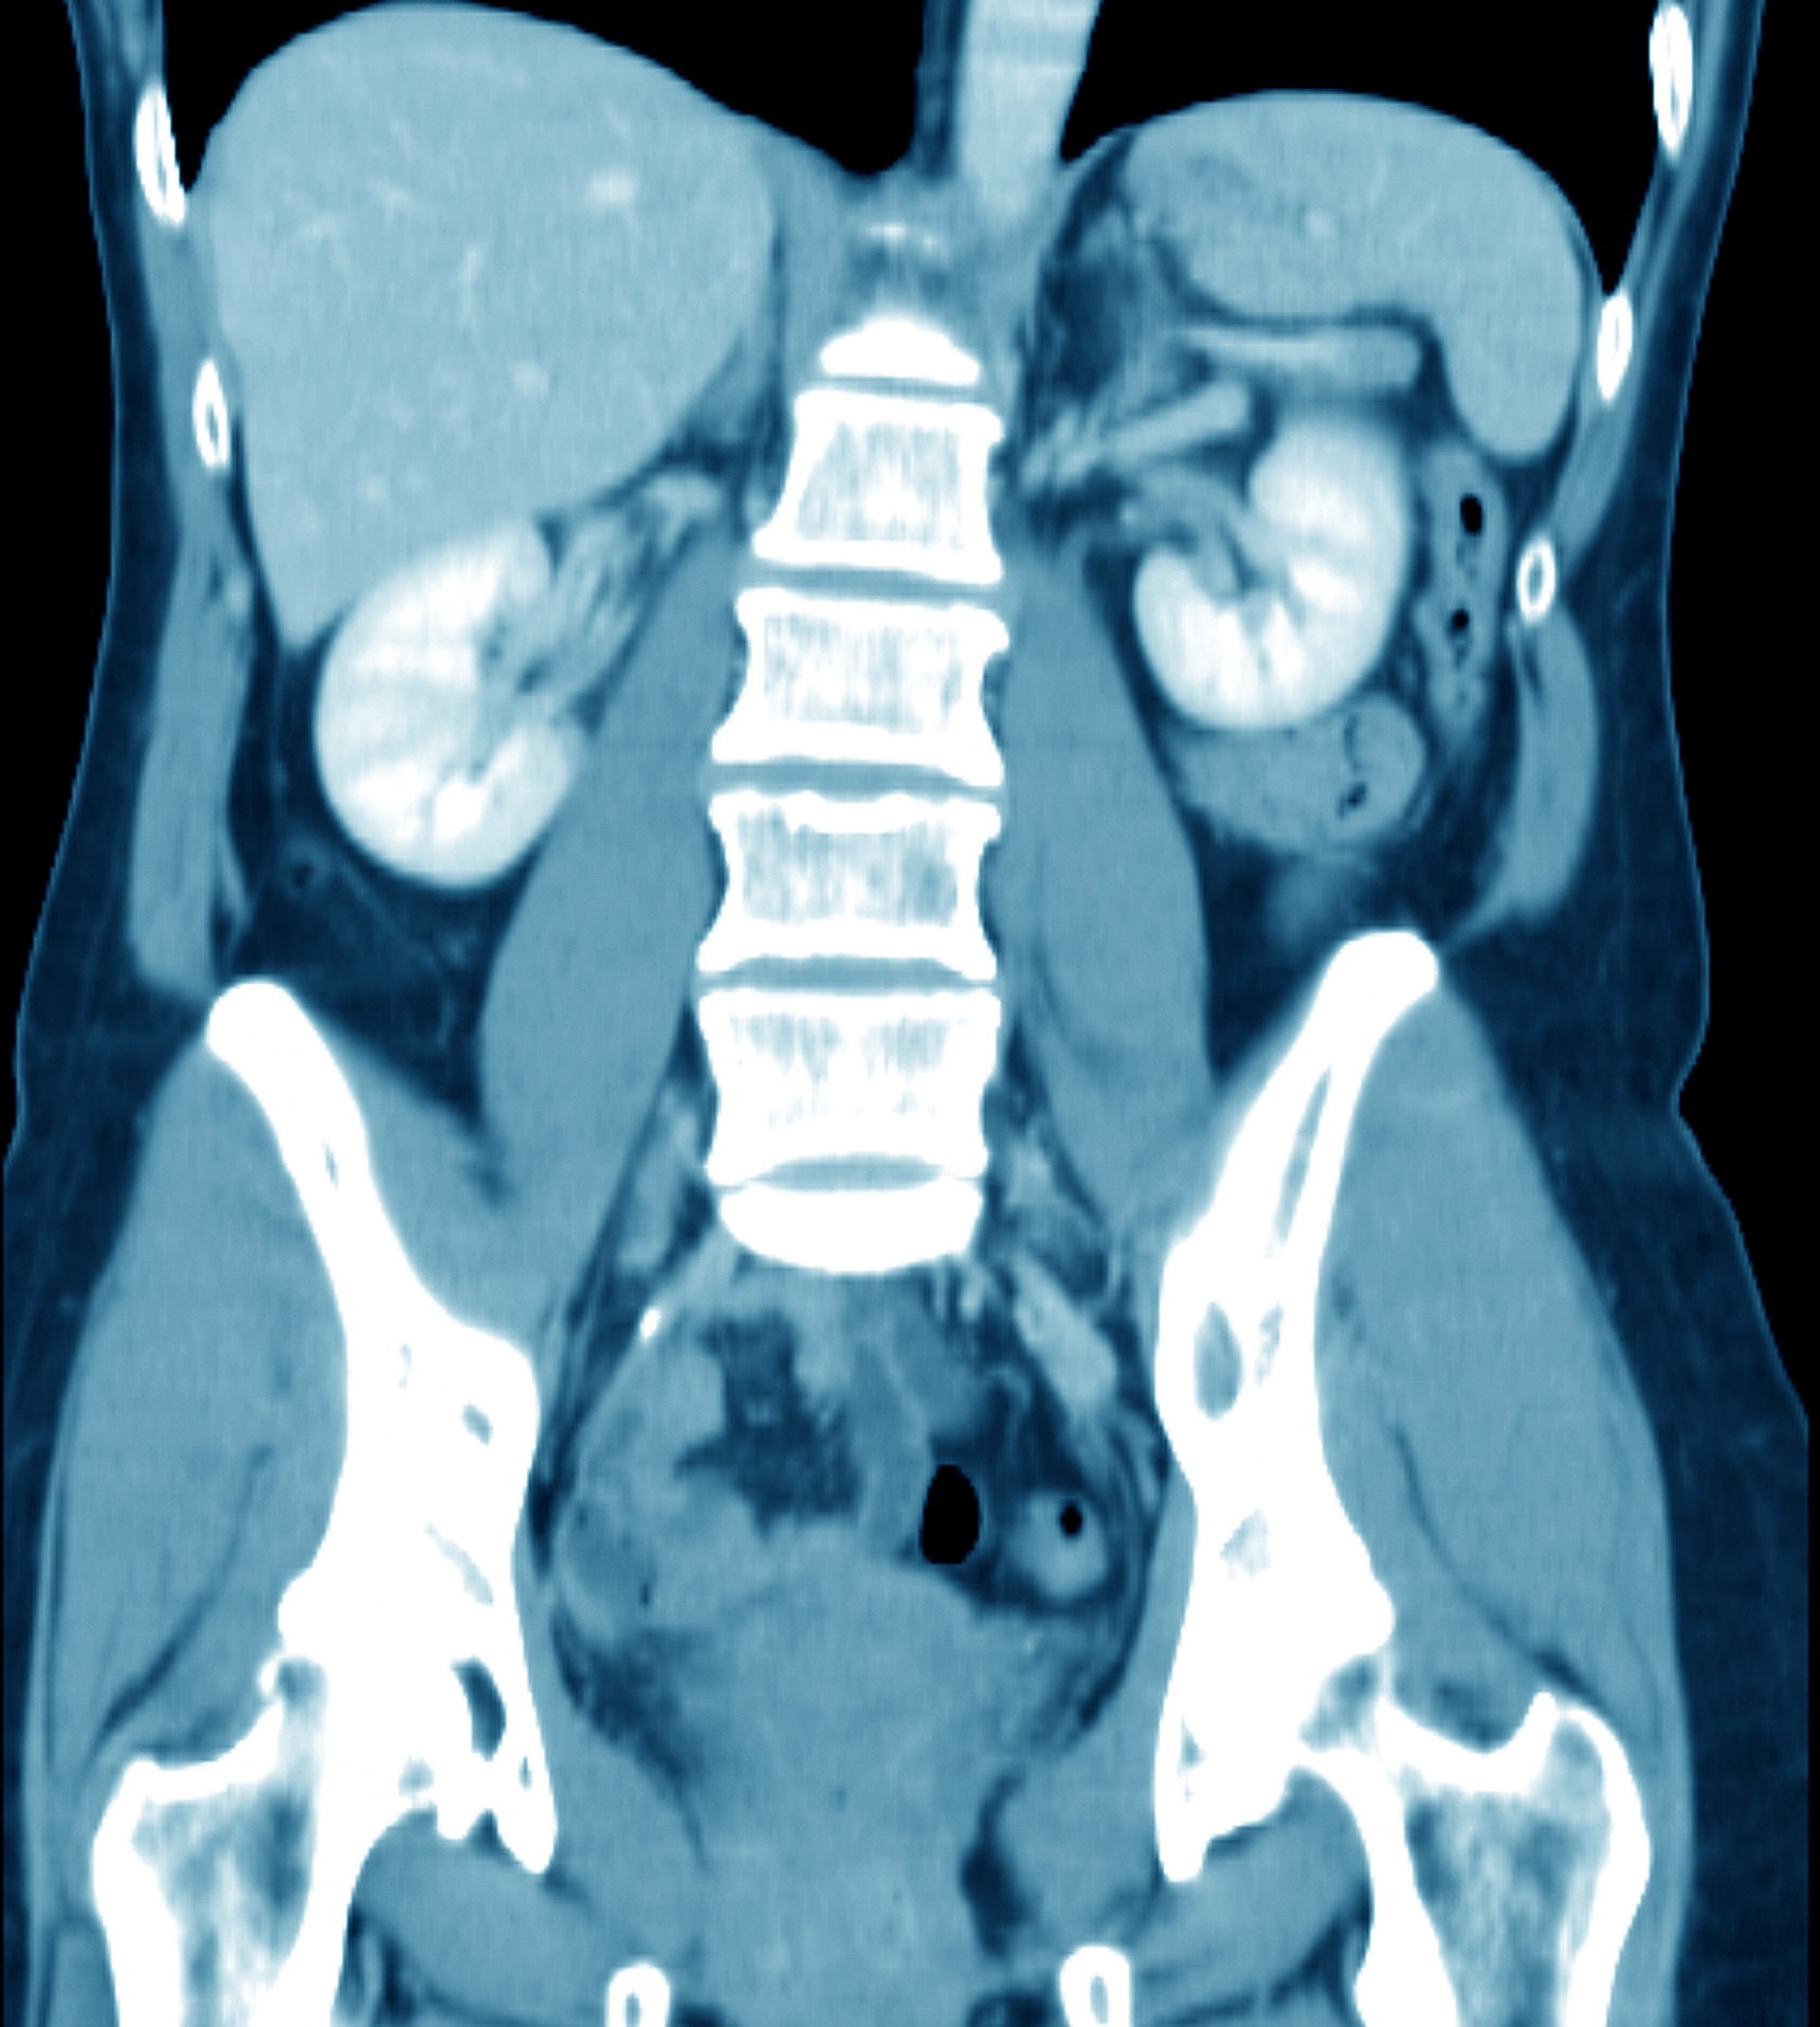

▼最後伊萬選擇了接受手術,同時搭配化療,可是不久後又復發,導致需要進行多兩次手術以切除腫瘤。在2018年他接受身體檢查時,發現肝臟的主要血管肝靜脈有新的繼發性腫瘤,由於之前3次手術已把他部分的肝靜脈切除,第4次手術恐要切除所有肝靜脈。

▼當時為他執刀的洛奇醫生表示,非常擔心伊萬的身體無法承受這樣的手術,也認為這場手術不會成功。可是在一次檢查中他發現伊萬之前接受肝臟切除手術的地方竟長出了新的靜脈,於是決定放手一試。

▼最後手術結果非常成功,伊萬的肝就依靠那條多長出來的靜脈所支持著,癌細胞都瞬間消失不見。洛奇醫生表示這個手術極度複雜,風險極高,是他所做過最困難的其中一個。也因為醫學上對於肝臟仍存在許多未知,他也稱這場手術是個世界首例的「醫學奇蹟」!